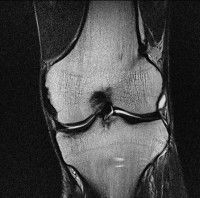

무릎 mri 간단히 봐주실 수 있으시나요 ㅠㅠ

안녕하세요 8년전 십자인대 수술하고 최근 무리한 운동에 무릎 불편감이 생겨서

mri 찍었습니다.

진단결과는 첫 찍은 병원에서 활액막염 이라는 진단을 받았습니다. 혹시 봐주실 수 있으실까요?

올라온 MRI가 단편적이라서 정확한 진단에 어려움이 있지만 십자인대에는 큰 이상이 있지는 않은것 같으며, 무릎관절내 물이 있는 것으로 보아 활액막염의 진단이 맞을 것 같습니다.

하지만 단편적인 영상이기 때문에 촬영병원에서 정확한 판독지 등을 받으시는 것이 좋겠습니다.